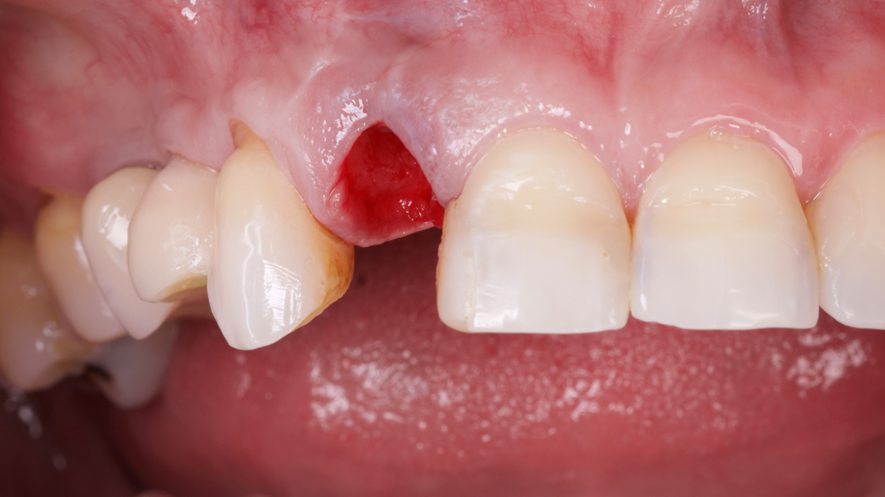

Este trabalho tem como objetivo relatar um caso clínico de exodontia minimamente invasiva de um incisivo lateral superior com fratura radicular, realizando implante imediato em alvéolo pós-extração, enxerto de tecido conjuntivo subepitelial e osso bovino liofilizado para preenchimento de GAP, prontamente à instalação de pilar reto e provisório imediato.